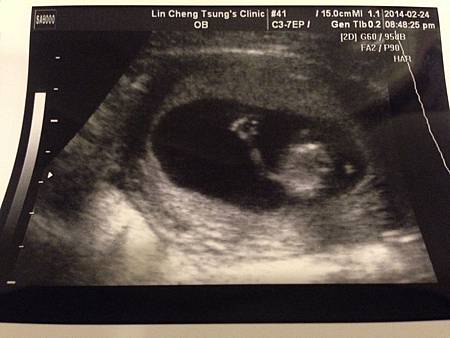

將將將將~我們家的「小馬子」滿三個月了,來跟各位叔叔阿姨說Hi了~他正在揮動他的小手,應該看得出來吧。還不知道性別,因為他今天夾得可緊了。不過如果是兒子可以叫馬子,如果是女兒更是她老爸的馬子,所以就先這樣暫時給他個暱稱吧。